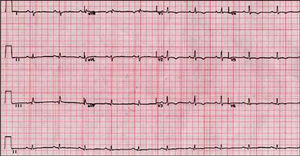

Las alteraciones del ECG más frecuentes son la inversión de la onda T (V1-V3), presente hasta en el 50% de los sujetos56. La afección más allá de V3 indica afección adicional del VI57 (fig. 1).

Fig. 1. Electrocardiograma de un paciente con miocardiopatía arritmogénica del ventrículo derecho y afección ventricular izquierda.

Existen diferentes anomalías de la despolarización descritas en la MAVD: el bloqueo de rama derecha incompleto es más frecuente (18%) que el completo (15%); la prolongación del QRS más de 110 ms en V1 y V2, un hallazgo más específico58, y la aparición de las ondas épsilon (fig. 2). Éstas se identifican en el 30%59, pero pueden pasar inadvertidas. La sensibilidad para su detección se puede aumentar con una adecuada preparación de la piel y obteniendo el ECG a doble velocidad y doble amplitud60. Se observan al final del QRS y al inicio del ST y corresponden a potenciales eléctricos retrasados de pequeña amplitud originados en las áreas de tejido sano rodeadas de infiltrado fibroadiposo61.